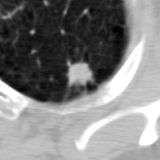

The current study focuses on lung nodule retrieval from a database of CT scans, where patches taken from CT slices of pulmonary nodules are to be mapped into an embedding. LIDC-IDRI [5] is a dataset of thoracic CT scans of 1,010 patients. All the scans were annotated by up to four radiologists, where each one identified, segmented and evaluated separately the lung nodules of a diameter above . Their evaluation also included ratings for a set of 9 characteristics: Subtlety, Internal structure, Calcification, Sphericity, Margin, Lobulation, Spiculation, Texture and Malignancy. The rating system was based on a discrete score of 1-5. Four examples of nodule patches are illustrated in Figure 2: 2 benign (a, b) and 2 malignant (c, d). A rounded vector of the mean rating is bellow each nodule, with the characteristics ordered according to the listing above. The most prominent difference between a and b is the calcification: 3 (solid) and 6 (absent) accordingly. d compared to c has a more defined margin, is more lobulated, but less spiculated. The malignancy score is used to define malignancy classes: score of 1-2 is benign, score of 3 is unknown, and a score of 4-5 is malignant.

(a) Benign

3, 1, 3, 3, 4, 3, 1, 5, 1

(b) Benign

3, 1, 6, 5, 5, 1, 1, 5, 2

(c) Malignant

5, 1, 6, 3, 3, 4, 1, 5, 5

(d) Malignant

4, 1, 6, 3, 4, 2, 2, 5, 4